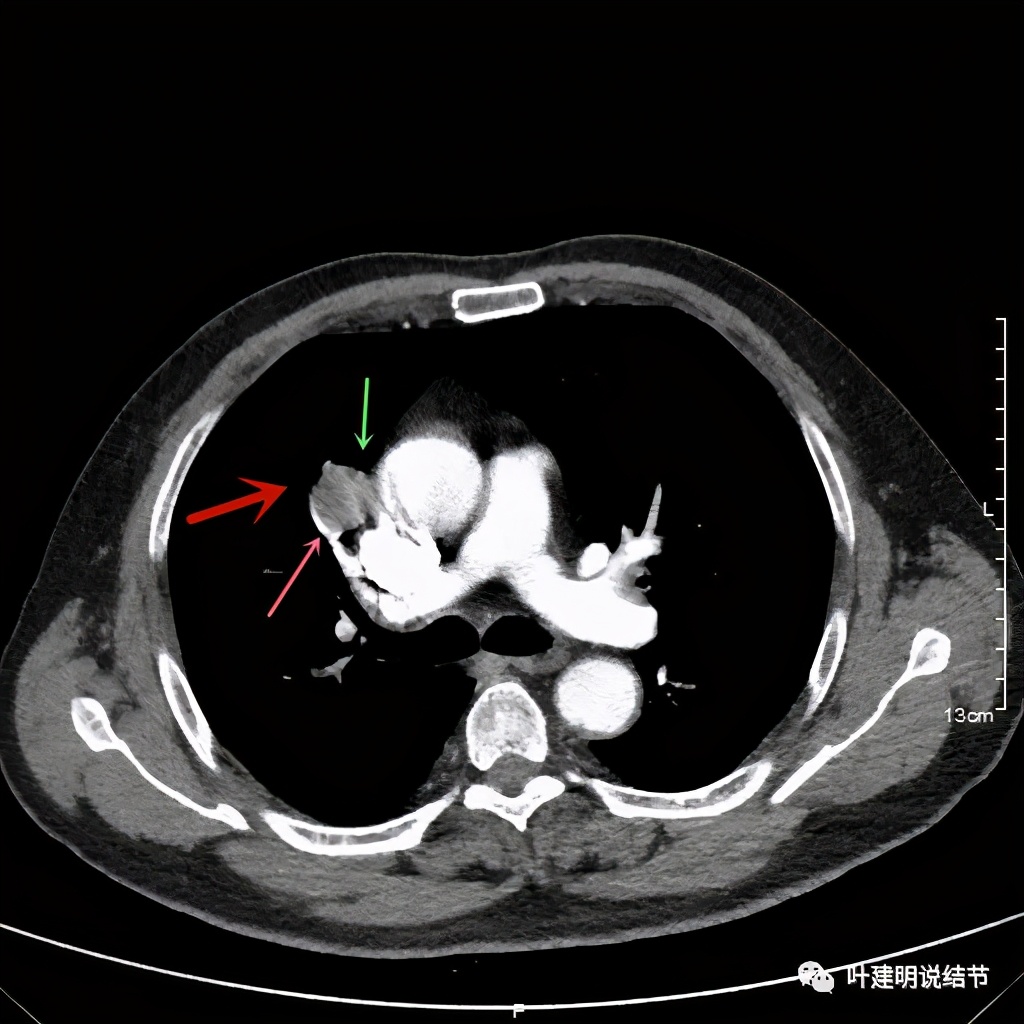

可见右上叶占位,我们现在知道了结果以后回头看,发现病灶的边缘在各个层面都是过于光滑(绿色箭头所示)。血管紧贴病灶边走行(桔色箭头所指),是不是有侵犯看不清楚,若是靶扫描加重建可能会更清楚点。支气管感觉也是贴着病灶走,但有的层面是不是截断,也不看的不太清楚。有的层面见局部有点状高密度(蓝色箭头所指),是不是错构瘤的局部钙化呢?若是纵隔窗又是如何?

上图示病灶

上图示病灶密度不均

上图示病灶局部点状高密度(蓝色);边缘过于光滑(绿色)

上图示病灶密度不均,但边缘过于光滑(绿色);支气管似有截断(粉色);局部有点状钙化(蓝色)

上图也示病灶密度不均,但边缘过于光滑(绿色);支气管似有截断(粉色);局部有点状钙化(蓝色)